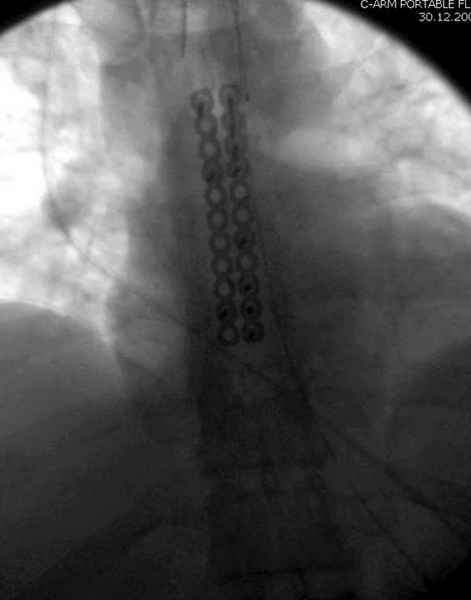

Юра, интересно, насколько такой остеосинтез контролирует степень репозиции, а то у меня имеются снимки девочки 11 лет, направленной ко мне на консультацию из одной из республик бывшего союза.

После торакальной операции, по-видимому, сильно натянули проволоку, и в результате получился захлест отломков в друг друга.

Оперировавший хирург предлагает подождать, а родителей беспокоит проблема прогрессирующей ассиметрии лица, как при кривошее.

С такими продольными несращениями мне не приходилось иметь дело, поэтому направил в один из центральных институтов детской ортопедии России.

А простые посттравматические ложные суставы грудины приходилось оперировать с ограничителем сверла и с фиксацией 2.4 мм пластинами с угловой стабильностью.